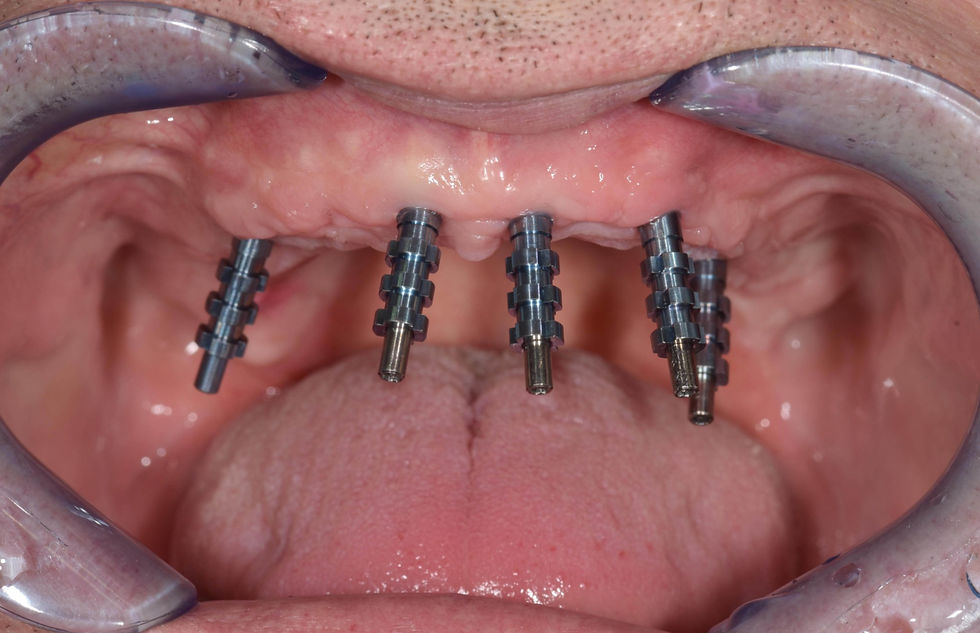

Open tray impression with Pick-up transfer.